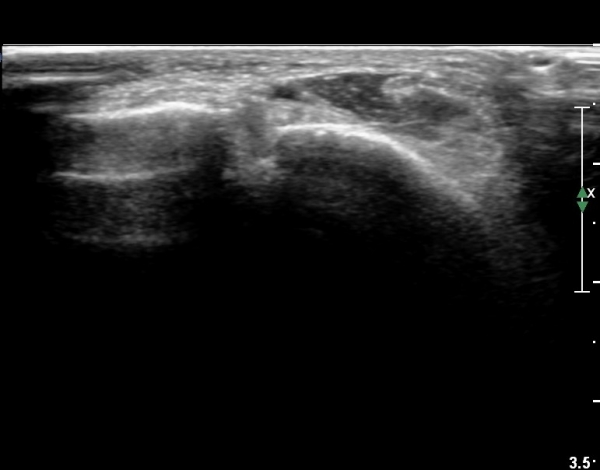

Àü¹æ ¸»´Ü °æ°ñºñ°ñÀδë Á¾´Ü¸é°Ë»ç¿¡¼­ ºñ°ñ ºÎÀ§ °æ°ñºñ°ñÀδëÀÇ Àú¿¡ÄÚºÎÁ¾ÀÌ °üÂûµÇ°í

ºÎÇϰ˻翡¼­ ºñ°ñÀÇ °úµµÇÑ ¿òÁ÷ÀÓÀÌ °üÂûµÈ´Ù(»çÁø 1, 2, µ¿¿µ»ó 1).